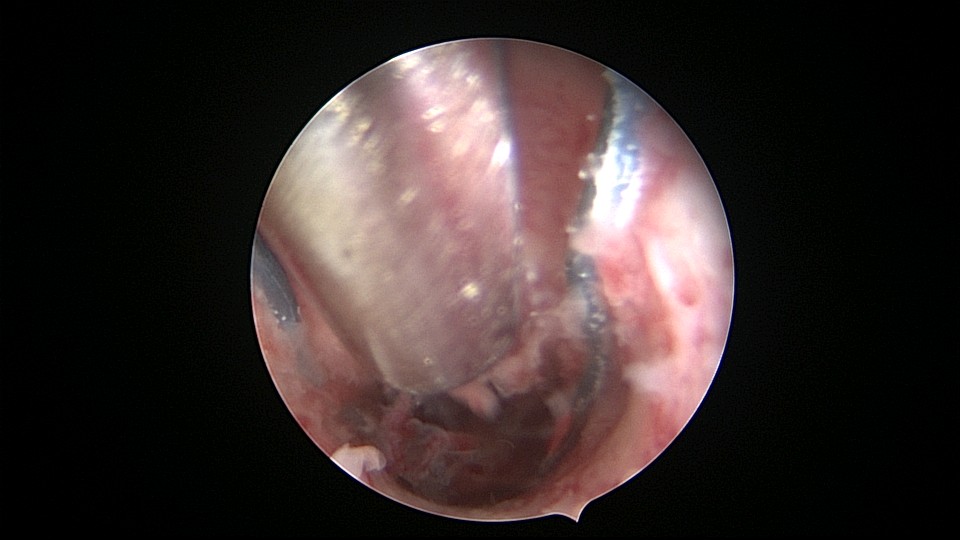

患者48岁,G5P1,剖宫产1次。安环20年,闭经3个月,外院取环失败,形成假道。子宫极度前倾前屈位,宫腔镜见宫颈管上段组织杂乱,左后壁假道,宫腔镜寻找到宫颈内口,艰难进入宫腔,爱母环位置正常,异物钳顺利取出,宫腔无其他异常。